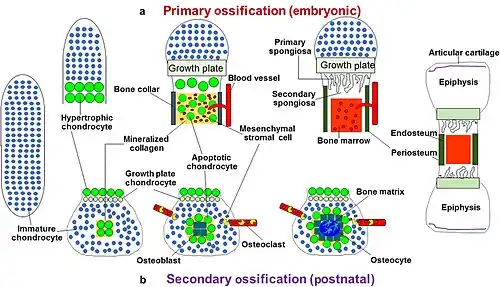

A schematic representation of endochondral ossification. | |

Endochondral ossification[1][2] is one of the two essential pathways by which bone tissue is produced during fetal development and bone repair of the mammalian skeletal system, the other pathway being intramembranous ossification. Both endochondral and intramembranous processes initiate from a precursor mesenchymal tissue, but their transformations into bone are different. In intramembranous ossification, mesenchymal tissue is directly converted into bone. On the other hand, endochondral ossification starts with mesenchymal tissue turning into an intermediate cartilage stage, which is eventually substituted by bone.[3]

Primary center of ossification

In developing bones, ossification commences within the primary ossification center located in the center of the diaphysis (bone shaft),[5] where the following changes occur:

- The perichondrium surrounding the cartilage model transforms into the periosteum. During this transformation, special cells within the perichondrium switch gears. Instead of becoming cartilage cells (chondrocytes), they mature into bone-building osteoblasts.[5] This newly formed bone can be called "periosteal bone" as it originates from the transformed periosteum. However, considering its developmental pathway, it could be classified as "intramembranous bone".[8]

- After the formation of the periosteum, chondrocytes in the primary center of ossification begin to grow (hypertrophy). They begin secreting:[10][11]

- Collagen type X, which causes stiffness and compression of the extracellular matrix.

- Matrix metalloproteinases.

- Vascular endothelial growth factor (VEGF), which controls forthcoming vascular invasion.

- Alkaline phosphatase, which causes calcification of the cartilage matrix. This calcification prevents passage of nutrients to chondrocytes leading to their death.

- When chondrocytes die, matrix metalloproteinases result in catabolism of various components within the extracellular matrix and the physical boundaries between neighboring lacunae (the spaces housing chondrocytes) weaken. This can lead to the merging of these lacunae, creating larger empty spaces.[8][9]

- Blood vessels arising from the periosteum invade these empty spaces and mesenchymal stem cells migrate guided by penetrating blood vessels. Following the invading blood vessels, mesenchymal stem cells reach these empty spaces and undergo differentiation into osteoprogenitor cells. These progenitors further mature into osteoblasts, that deposit unmineralized bone matrix, termed osteoid. Mineralization subsequently follows leading to formation of bone trabeculae (Endochondral bone formation).[11]

Secondary center of ossification

During the postnatal life, a secondary ossification center appears in each end (epiphysis) of long bones. In these secondary centers, cartilage is converted to bone similarly to that occurring in a primary ossification center.[8] As the secondary ossification centers enlarge, residual cartilage persists in two distinct locations:[11]

- Articular cartilage: This layer coats the bone ends, concerned with joint movement.

- Epiphyseal growth plate: This transverse layer lies between the epiphysis and diaphysis. It’s composed of highly active chondrocytes and responsible for longitudinal bone growth. Consequently, the bone elongates at this growth plate until closure occurs at skeletal maturity.

At the end of an individual’s growth period, the production of new cartilage in the epiphyseal plate stops. After this point, existing cartilage within the plate turns into mature bone tissue.[8]

Process of endochondral ossification.

Process of endochondral ossification. -